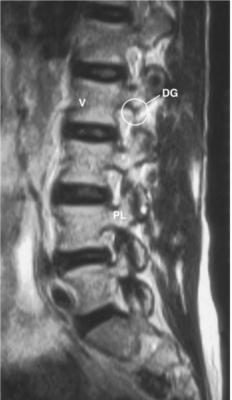

Cột sống thắt lưng

Các chữ viết tắt:

- DG = Dorsal root ganglion of L2 in intervertebral foramen

- PL = Pedicle; cuống cung

- V =Vertebral body; Thân đốt sống